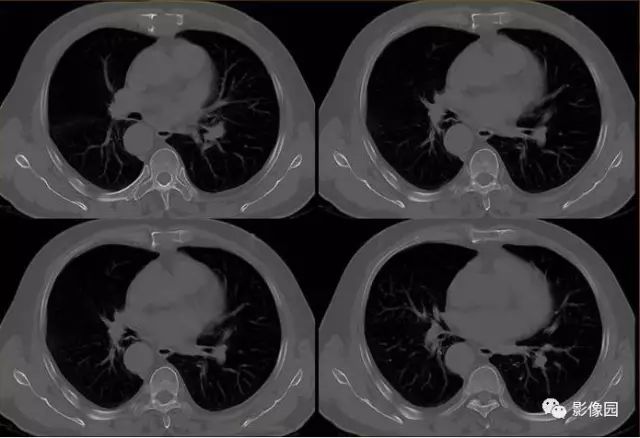

胸骨浆细胞骨髓瘤1例CT影像表现

【基本资料】男,66岁

【主诉】发现胸骨隆起1年余

【现病史】患者于1年前发现胸骨局部隆起,无红肿热痛,当时未予治疗,近来自觉隆起明显增大,伴胸前区隐痛不适。

【专科检查】胸骨上段局部隆起,压痛明显,胸部呼吸运动正常

肚肚丫头: 胸骨体局部呈膨胀性骨质吸收破坏,内呈软组织密度影,可见点状钙化,增强扫描呈轻度强化,周围软组织略肿胀。考虑:1.骨巨细胞瘤;2.浆细胞瘤;3.嗜酸性肉芽肿

【病理结果】(胸骨占位)符合浆细胞骨髓瘤

CT表现:特征性穿凿状、鼠咬状及蜂窝状骨破坏,边缘清楚,骨质疏松,病理性骨折及软组织肿块等表现,骨质硬化及骨膜反应少见。

骨破坏区完全为软组织取代,骨质膨胀,边界清楚,常突破骨皮质形成软组织肿块。增强扫描可见病灶轻中度强化,一般于静脉期达峰值。